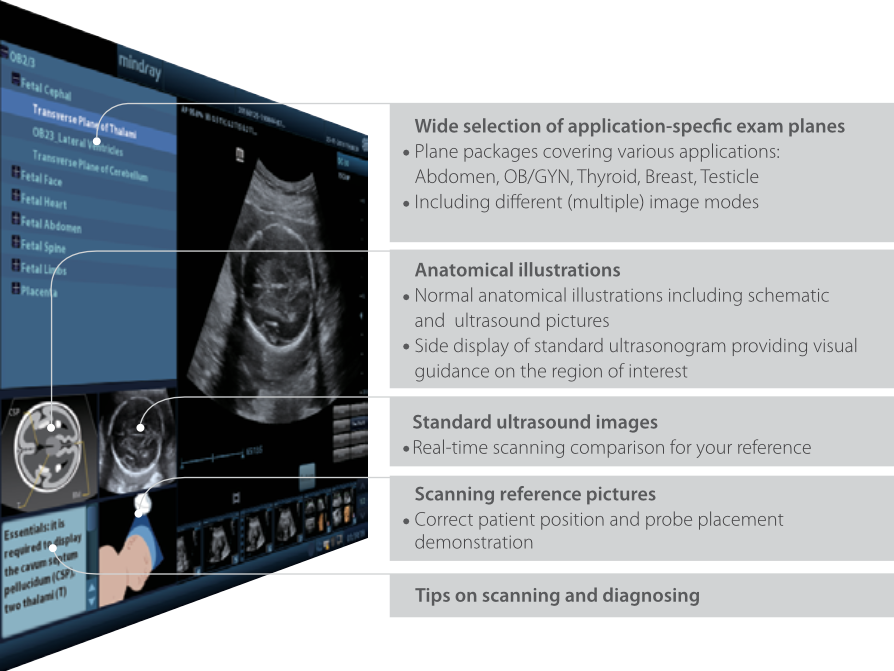

iScanHelper

Herramienta instructiva incorporada que ofrece a los usuarios informaciĂłn bĂĄsica sobre ecografĂas. iScanHelper incluye ilustraciones anatĂłmicas, imĂĄgenes estĂĄndares de ultrasonidos y de referencia de escaneo, y sugerencias para el escaneo adecuado.